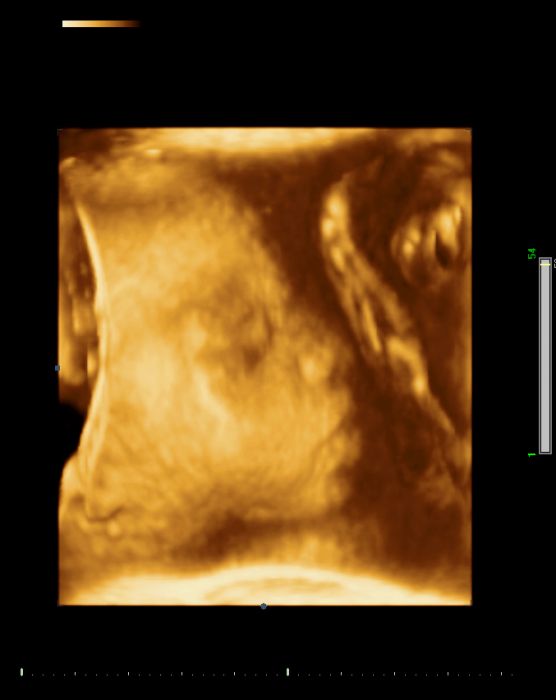

[367955] Jsem 28tt :-) Včera jsme byly na 3D...malá se na nás nechtěla moc dívat...ale zadeček nám ukázala, tak máme potvrzeno, že to bude malá slečna :-)